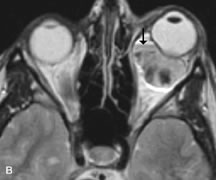

Intraorbital and intracranial optic nerve sheath meningiomas are usually isointense to cortical gray matter on Tl-weighted images and remain isointense on proton density studies (Fig. 15). Gd-DTPA is useful in delineating the intracranial extension of optic nerve meningiomas.7,47 The hyperostosis of bone and calcification associated with meningiomas are not demonstrated as well on MRI studies as on CT scans.20,37 Gd-DTPA–enhanced MRI also appears promising in the study of the permeability of the blood–brain barrier in selected optic neuropathies.22,48 MRI may reveal an enlarged optic nerve and some degree of contrast enhancement in cases of optic neuritis.49

Fig. 15. A. T1- and (B) T2-weighted MR scans demonstrate a mass causing fusiform enlargement of the optic nerve sheath complex. The peripheral portion of the mass, representing the meningioma, is isointense to brain on the T1-weighted scan and notably hypointense on the T2-weighted scan. The central portion of the mass, representing an edematous optic nerve, is very hyperintense on the T2-weighted scan (arrow), C and D. Postcontra fat-suppressed T1-weighted scans demonstrate intense peripheral enhancement of the meningioma surrounding the central nonenhancing optic nerve (arrow). Also note the enhancing Intracranial “dural tail” (double arrow).